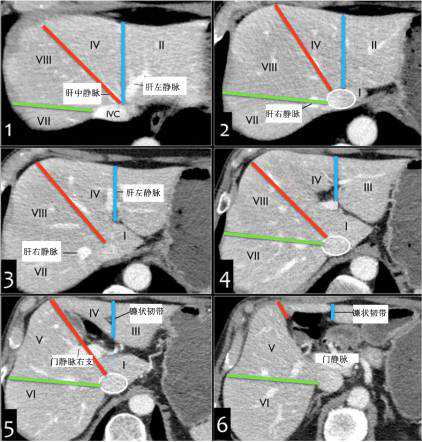

二、横断面解剖图示

(1)肝上部水平:由肝中静脉、肝右静脉、镰状韧带分段。

(2)门静脉左支水平:门静脉左支将肝分为上下部分,上方II和Iva,下方III和IVb。门静脉左支比右支位置高。

(3)门静脉右支水平:该水平门静脉右支将肝右叶分为上部(VII和VIII)和下部(V和VI)。

(4)脾静脉水平:脾静脉较门静脉右支低。可见III、IVb、V、VI段。

CT轴位分段

肝左右叶(IV段与V、VIII段)分界:沿胆囊窝上方肝中静脉至下腔静脉(下图红线)。

肝左叶(内侧II、III段与外侧IV段)分界:沿镰状韧带和肝左静脉、肝中静脉汇合处下腔静脉连线(下图蓝线)。

肝右叶(前侧V/VIII段与后侧VI/VII段)分界:沿下腔静脉下方肝右静脉至肝脏边缘(下图绿线)。

尾状叶:尾状叶(I段)在后方,尾状叶与其他叶不同的是,它经常经静脉直接与下腔静脉,而不通过肝静脉主干,也有可能同时接受门静脉左右支的血供。(下图C)